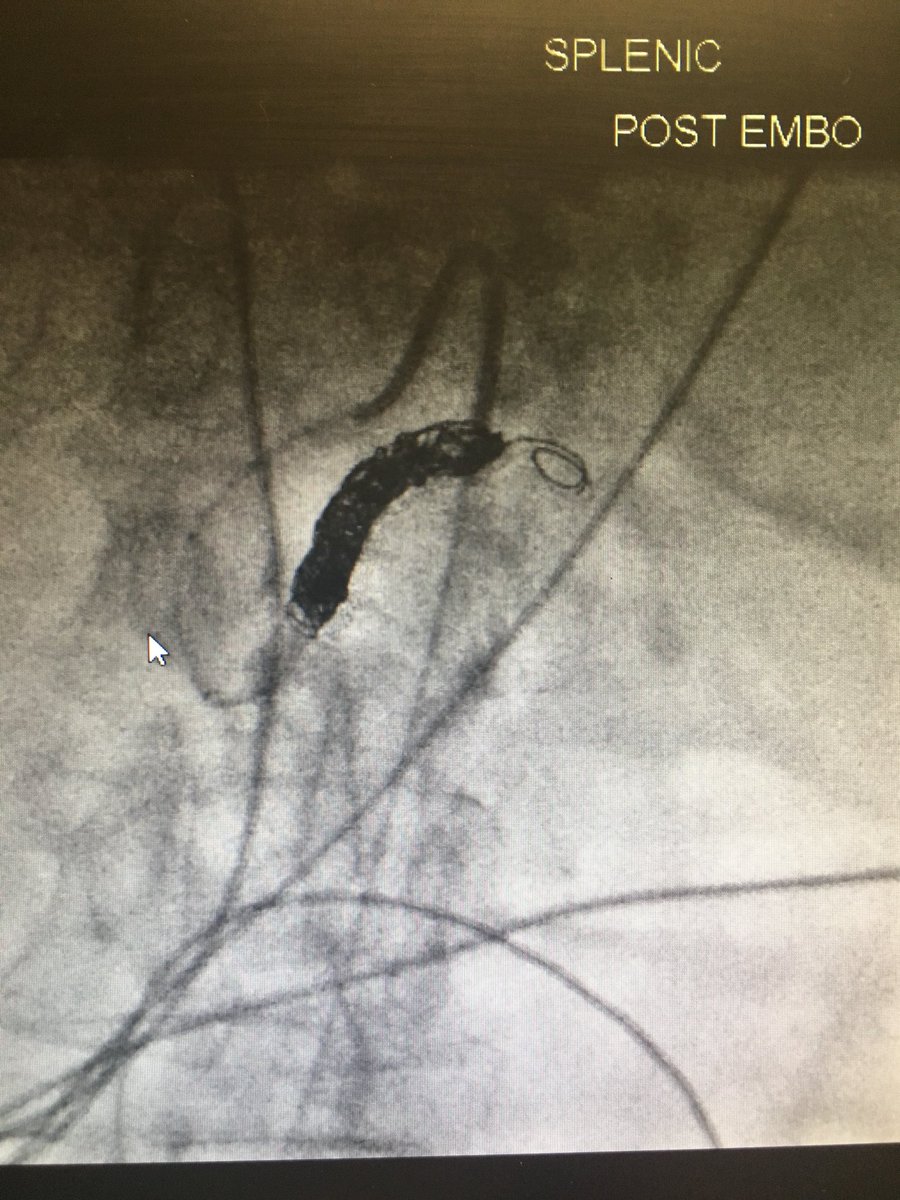

Renal pseudoaneurysm embo after MVA Saturday, proximal splenic artery embo after fall on Sunday, liver embo after GSW tonight...can’t wait to see what Tuesday brings! #withoutascalpel #womeninIR #IRad @Priddy_IR @Chando_RadMD @UofLRadiology